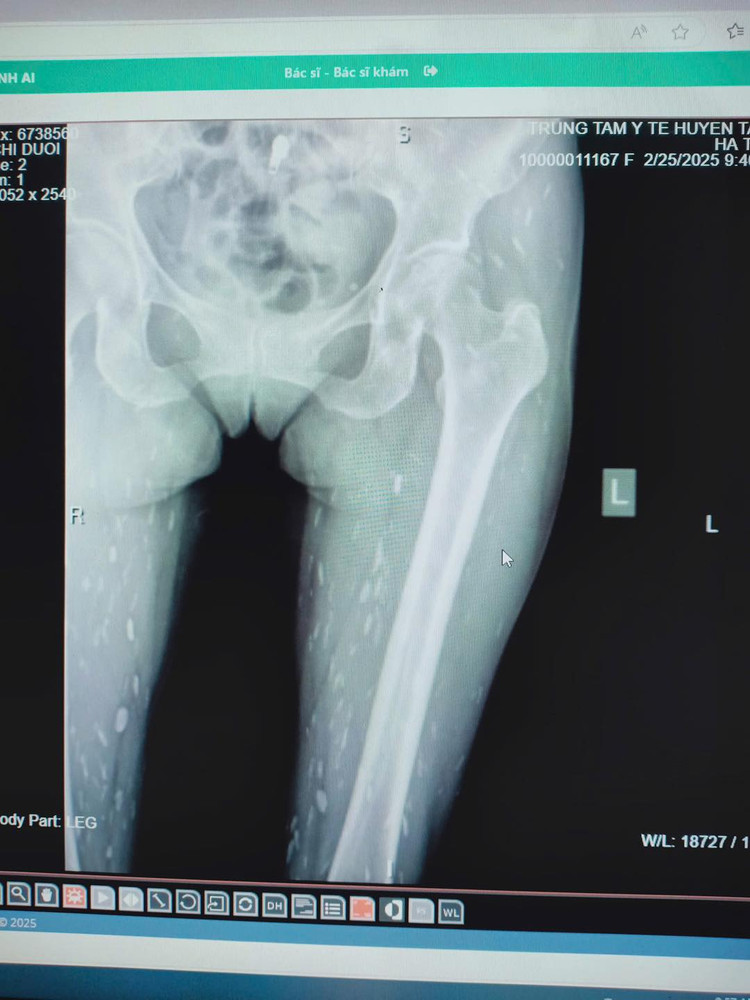

| Chi chít sán trong não bệnh nhân. Ảnh Trung tâm Y tế huyện Tân Sơn |

Bệnh sán não xảy ra khi kén sán có ở não từ một đến nhiều ổ. Mức độ tổn thương nặng hay nhẹ phụ thuộc vào số lượng kén sán có trong não. Biểu hiện thường gặp là: bệnh nhân bị nhức đầu, buồn nôn hoặc nôn, cơn co giật (động kinh), liệt nửa người hoặc tê bì rối loạn cảm giác, khó ngủ hoặc mất ngủ, mờ mắt, tăng áp lực sọ não, suy nhược thần kinh, rối loạn tâm thần, bệnh nhân có thể bị đột tử.